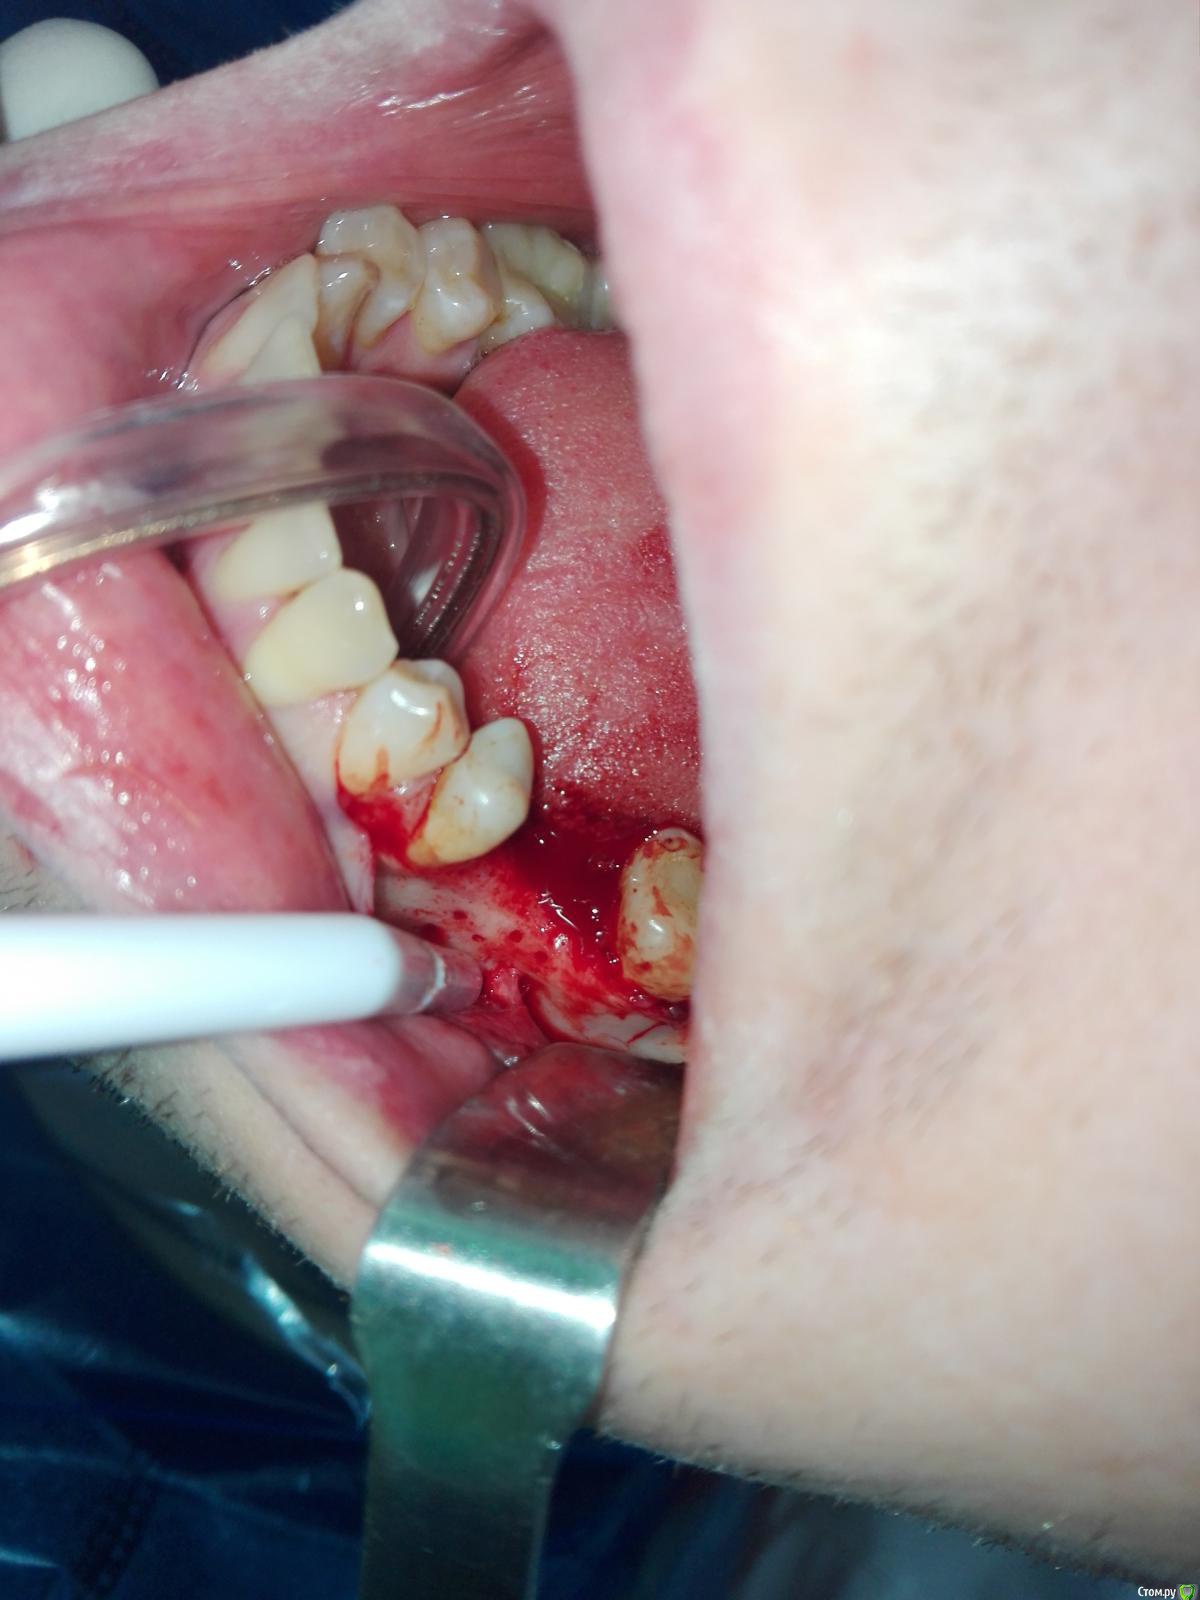

karasov Опубликовано 20 октября, 2016 Поделиться Опубликовано 20 октября, 2016 (изменено) В области 36 работал с ламиной. Наткнулся на нерв. Причем два. Один обошел , второй нет. Что ждать?на кт ееееле заметны Изменено 20 октября, 2016 пользователем karasov Ссылка на комментарий

kriokov Опубликовано 21 октября, 2016 Поделиться Опубликовано 21 октября, 2016 Наткнулся на нерв. не похож на нерв. имхо. Ссылка на комментарий

karasov Опубликовано 21 октября, 2016 Поделиться Опубликовано 21 октября, 2016 не похож на нерв. имхо.По кт есть однозначно связь с нижним альвеолярным. Визуально на сосуд не похоже Ссылка на комментарий

karasov Опубликовано 21 октября, 2016 Поделиться Опубликовано 21 октября, 2016 Слева был, справа есть Ссылка на комментарий